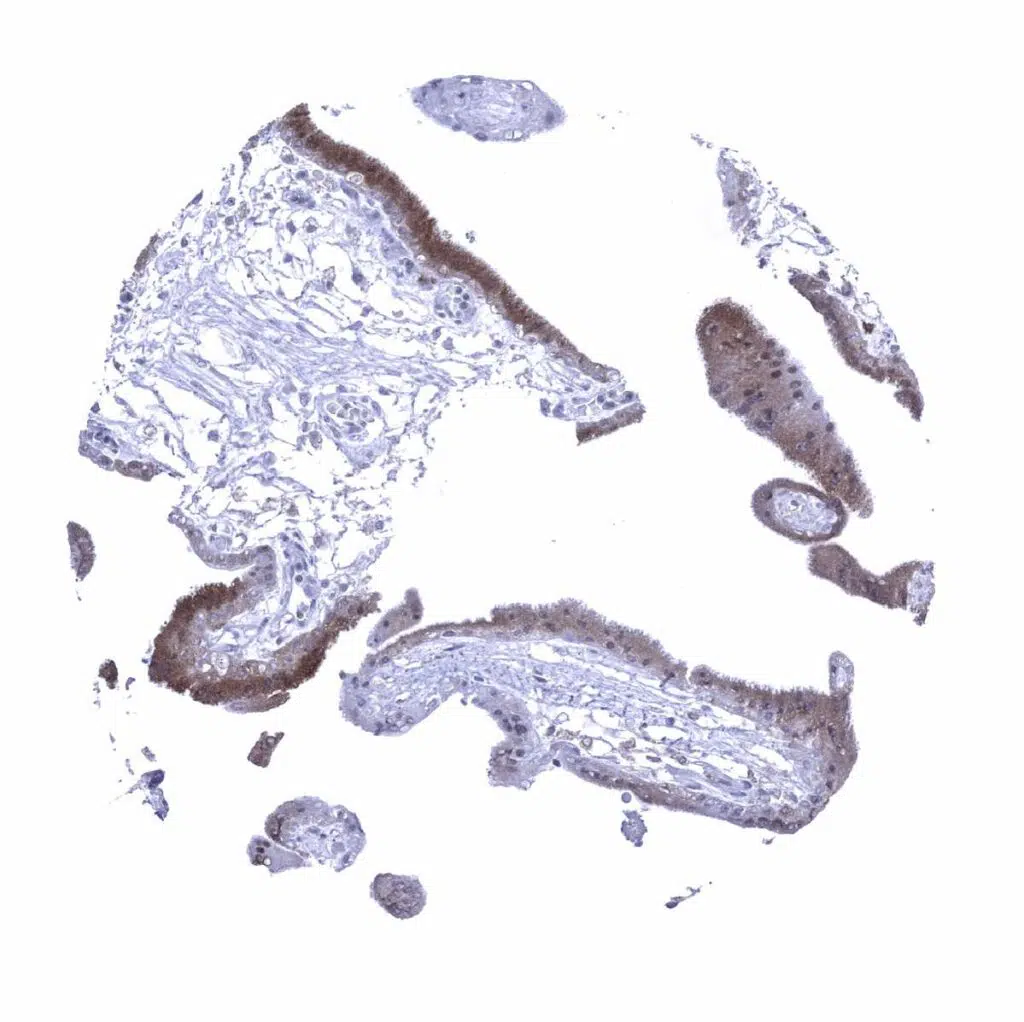

Placenta (amnion and chorion) – Chorion and amnion cells are negative but some decidua cells show a weak to moderate GS staining